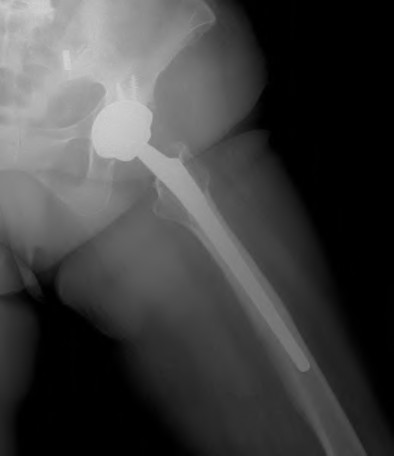

A 72-year-old female presents with progressive left thigh and knee pain for the last year. 5 years ago she sustained a femoral neck fracture treated with the implant seen in Figures A-C (current radiographs). The thigh pain is worse with weight-bearing. C-reactive

protein and erythrocyte sedimentation levels are within defined limits. Which of the following is the most likely cause of her pain?